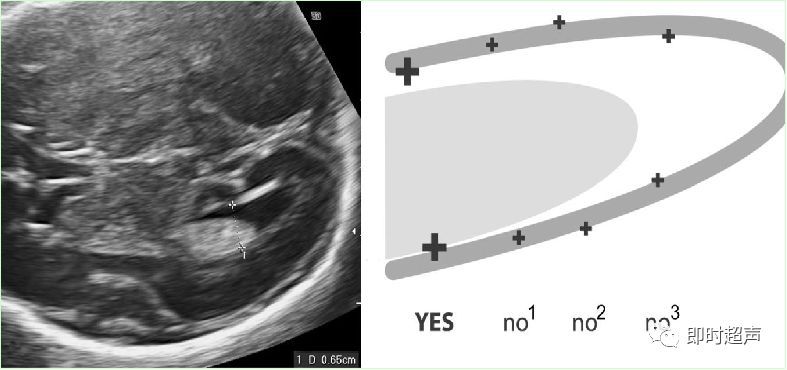

NT定义:颈项透明层指胎儿颈椎水平矢状切面皮肤至皮下软组织之间的最大厚度NT反映皮下组织内淋巴液体的积聚。

测量时间: 在孕 11 – 14周。胎儿头臀长 45 ~84mm时进行。

超声测量NT:多数专家认为NT 增厚定义为厚度超过第 95 百分位数,不论NT 是否有分隔,也不论是局限性或全身性,即 NT≥3.0mm作为异常增厚的标准。